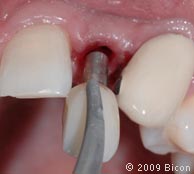

26. Для раскрытия верхнего бокового правого резца сделан надрез.

27. Извлечение заглушки с помощью специального инструмента.

28. Извлечение заглушки с помощью специального инструмента.